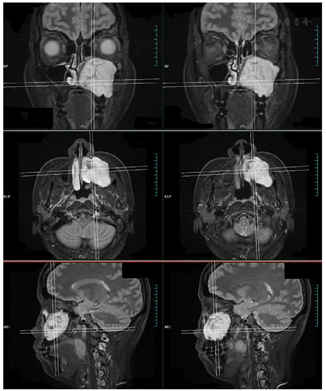

3.辅助检查∶ 2019年9月16日我院鼻窦MRI+增强示左侧上颌窦扩大,内可见团状软组织信号影充填,T1以低信号为主,对应T2WI呈中高信号,T1内可见散在斑片状稍高信号,对应T2WI呈低信号,病灶边界清楚,边缘呈分叶状,病灶大小约50.1 mm×40.6 mm×47.0 mm,增强扫描病灶边缘强化,内未见明确异常强化。左侧上颌窦诸壁骨质可见膨胀性吸收破坏,窦底局部骨质欠连续,考虑左侧上颌骨囊肿可能。